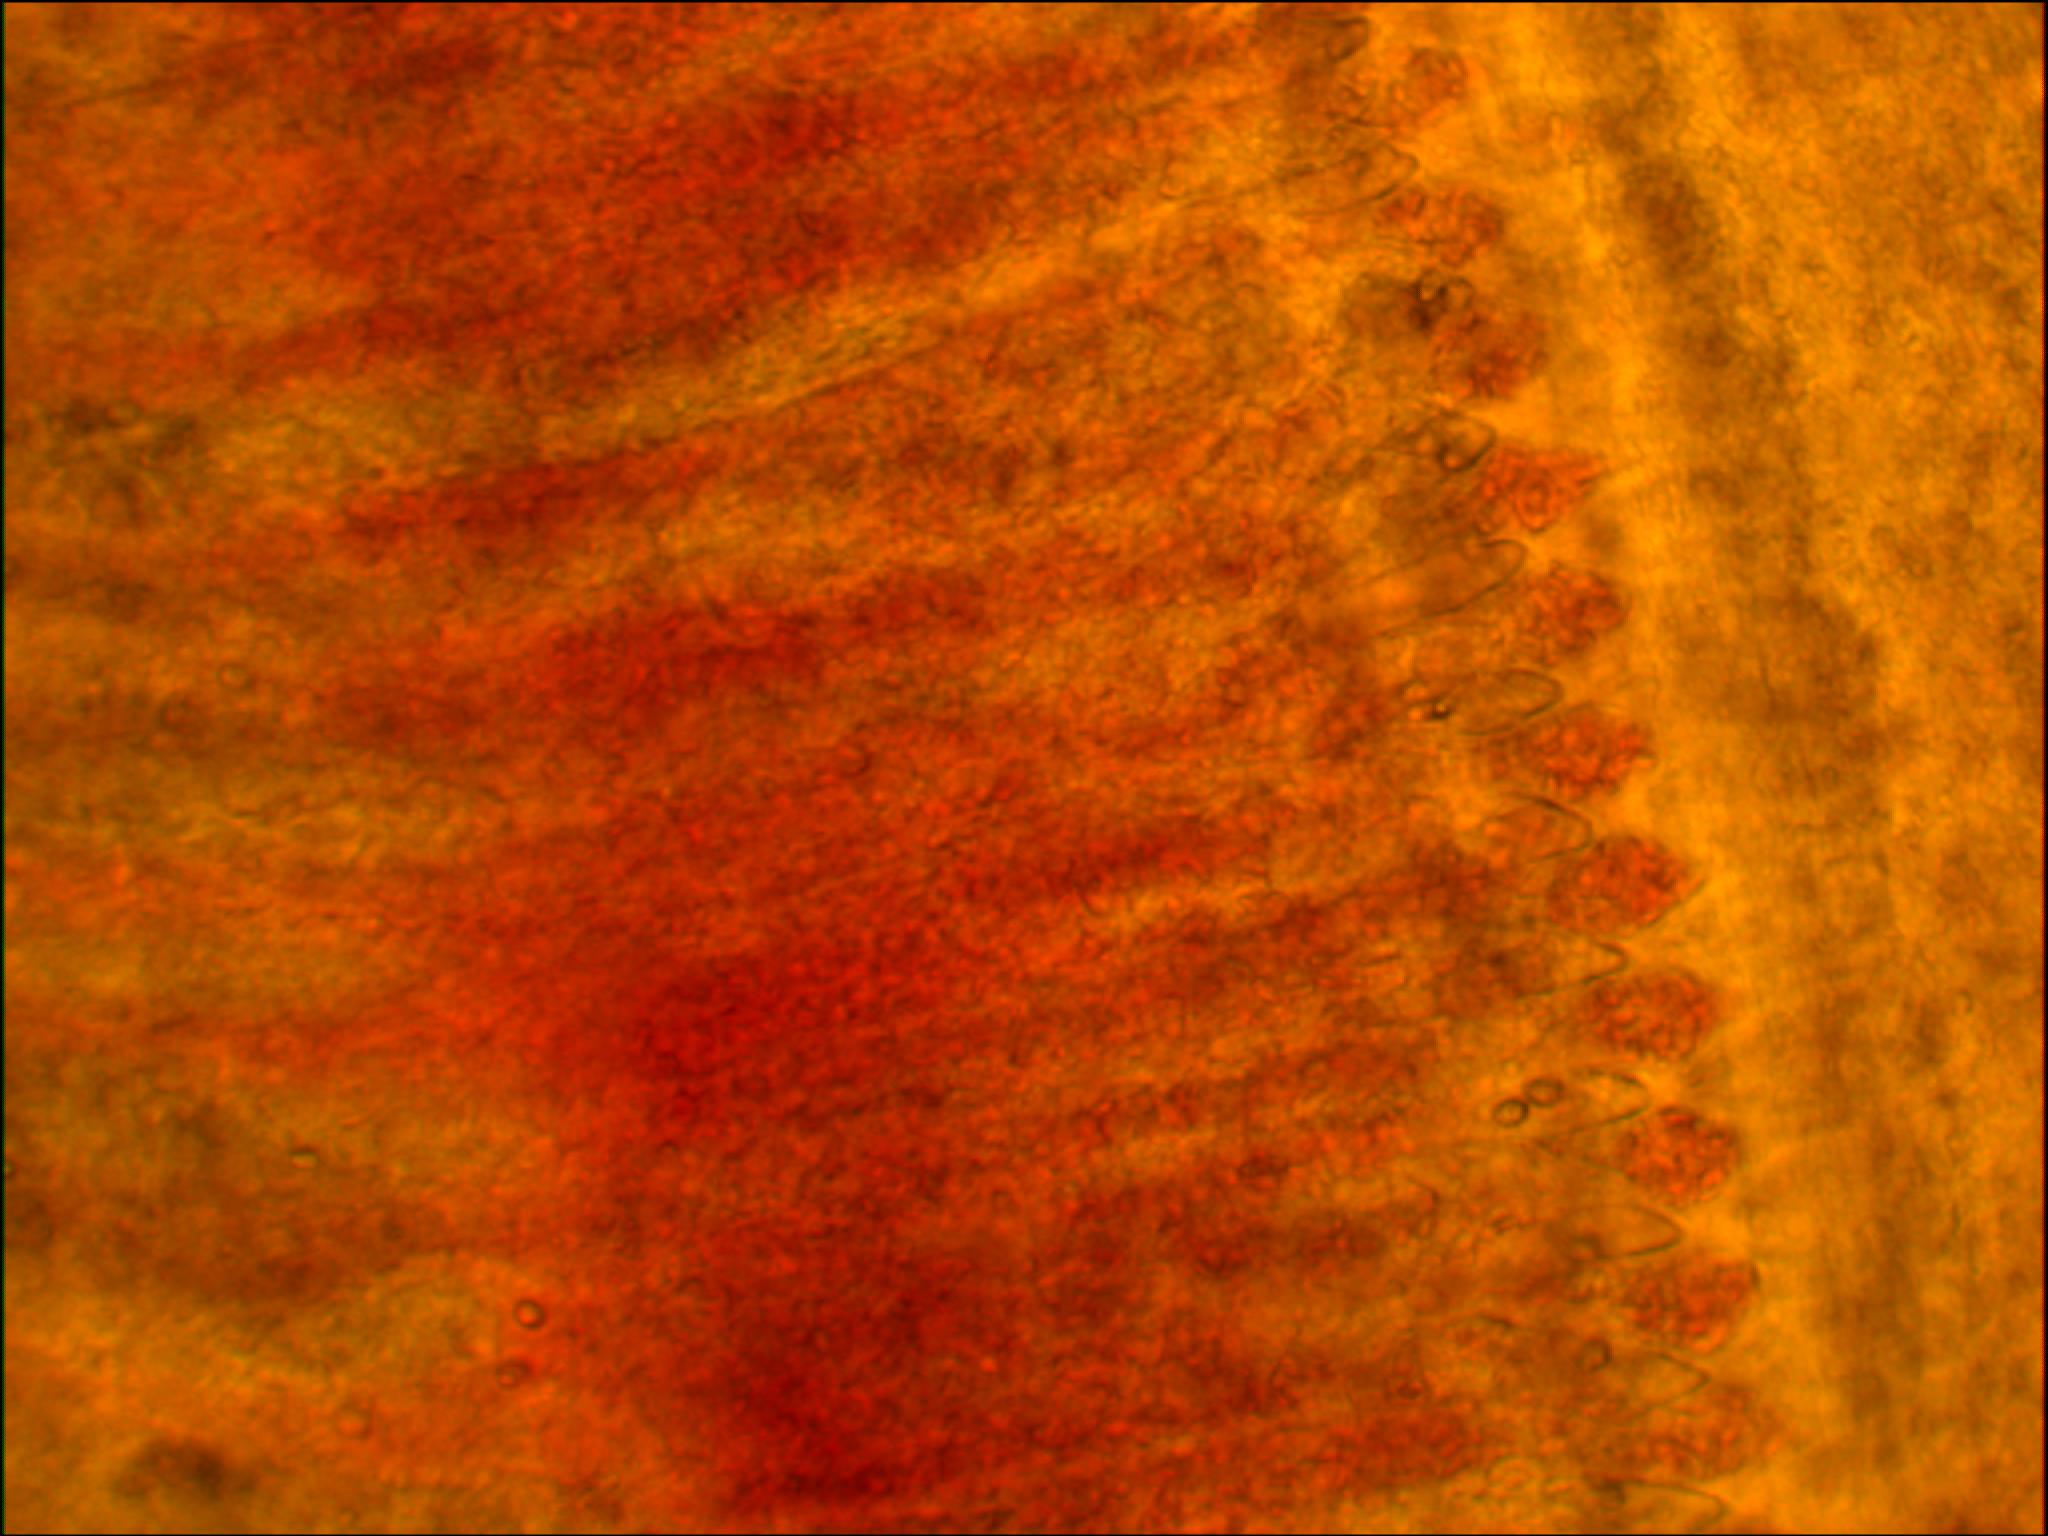

Гибель карпов началась с нескольких экземпляров и достигла 50 кг в день в течение недели. Рыбы скапливались у водоподачи и держалась у поверхности воды. Пораженные жабры были чаще мраморные, слегка отечные, растрепанные, иногда частично разрушенные, покрыты слизью (рис. 1-1). Часто фрагменты жаберного эпителия отшелушивались (рис. 1-2) вместе с одноклеточными круглыми или овальными образованиями.

Гистопатологические изменения в жабрах проявлялись в виде гиперплазии и гипертрофии жаберного эпителия.

Большинство жаберных лепестков имели на своих верхушках опухоли, обладающие неоднородной структурой. Часть опухолей имела однородную структуру и состояла из мелких, плотно расположенных клеток. Для большей части жаберных лепестков (около 90 %) было характерно двустороннее разрастание многослойного плоского эпителия. При этом происходила изоляция большей части жаберных лепестков от внешней среды. Свободными оставались лишь концы жаберных лепестков. На некоторых участках жаберных лепестков (на верхушках или реже в середине) отмечалось разрастание многослойного плоского эпителия. Данное образование имело уже вид «эпителиальных пластинок». Подобные изменения в строении жаберных лепестков приводят к нарушению функции газообмена, что нередко приводит к асфиксии.

Патологические изменения жаберных лепестков проявлялись в виде Г-образной формы, на концах которых отмечалась гипертрофия респираторных эпителиоцитов. «Раздвоение» ламелл нередко сопровождалось «слипанием» концов, а также некрозом мышечной и хрящевой ткани. Было отмечено большое количество клеток слизи.